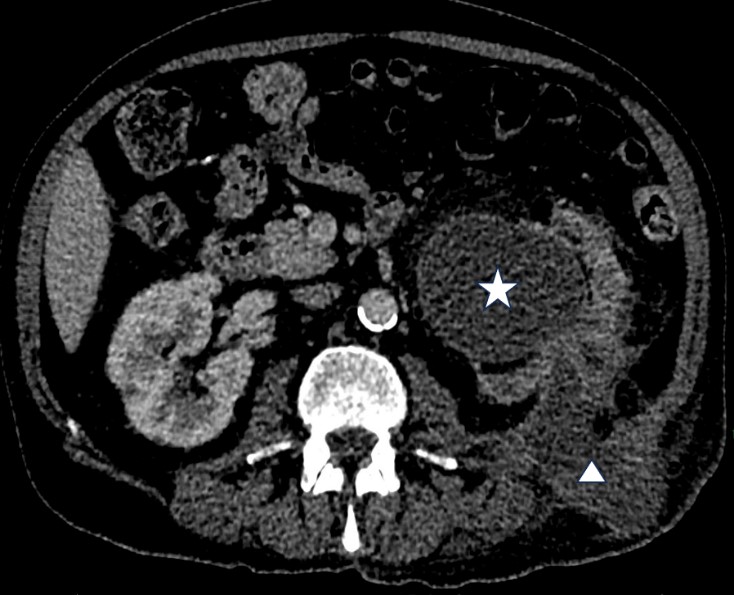

Computed Tomography (CT) confirmed the ultrasound findings of a large, multiloculated collection extending posteriorly from the left kidney through several fascial planes to the skin surface (Fig5). CT report stated that while this may be suggestive of an extensive renal abscess development with a sinus tract extending to the skin surface, a malignancy remained a differential.

| Figure 5: CT image of the left renal abscess extending through the posterior abdominal wall facia to the dermis of the left flank. (Star: Hydronephrotic kidney, Triangle: Sinus tract extending through the posterior musculature of the abdominal wall to the skin surface) |